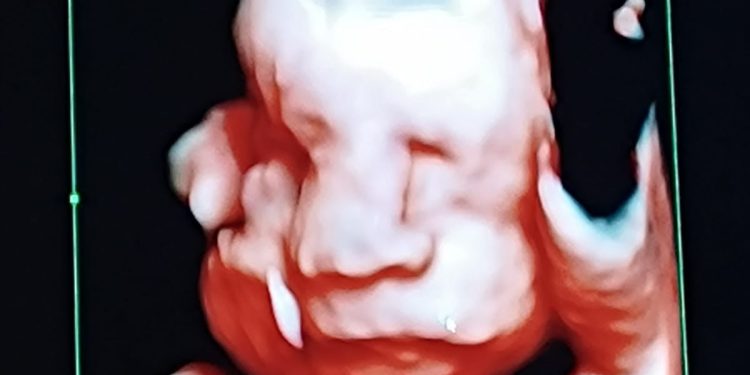

Este miércoles 22 de octubre, en horas de la tarde, el Hospital Central del Instituto de Previsión Social, registró el nacimiento de trillizos masculinos mediante cesárea de urgencia en el contexto de una gestación monocorial triamniótica (una sola placenta y tres bolsas amnióticas), la cual es considerada de alto riesgo y debe permanecer bajo control especializado desde el primer trimestre del embarazo.

Durante el seguimiento prenatal, uno de los fetos presentó una restricción selectiva del crecimiento intrauterino (RCIU) a las 17 semanas de gestación. Esta condición se produce cuando uno de los bebés crece más lentamente que los demás debido a una distribución desigual del flujo sanguíneo o de los nutrientes dentro de la placenta compartida.

El cuadro fue manejado mediante controles seriados de ecografía Doppler y monitoreo evolutivo semanal, logrando la normalización progresiva del crecimiento fetal a partir de la semana 22 y una evolución favorable de los tres fetos en los controles posteriores.

A las 30 semanas y 4 días de gestación, se decidió interrumpir el embarazo mediante cesárea de urgencia debido a una complicación materna por hipertensión arterial, pese al tratamiento profiláctico con ácido acetilsalicílico (AAS) 150 mg. La intervención se realizó de manera oportuna priorizando la seguridad materno-fetal.

Los recién nacidos, todos de sexo masculino, presentaron signos de vitalidad al nacer y fueron derivados al Servicio de Neonatología para recibir cuidados especializados acordes a su prematurez.